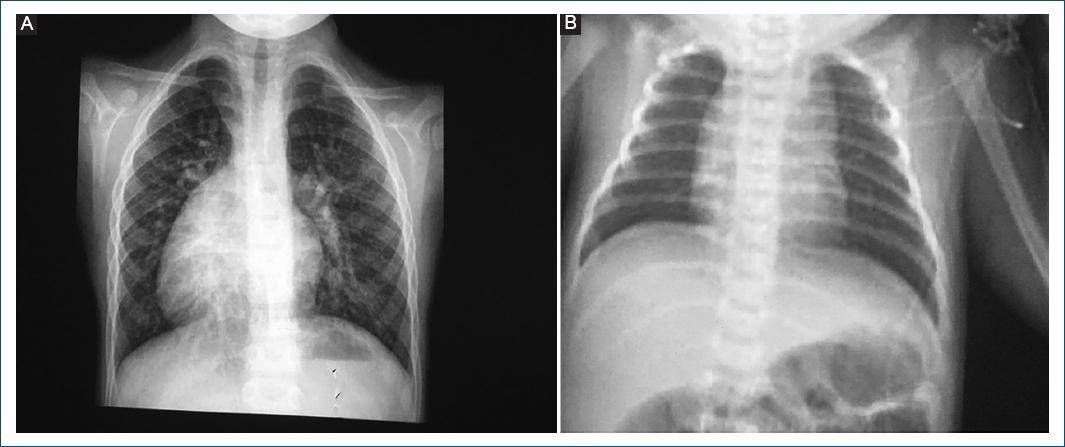

En la radiografía se puede presentar hipertrofia del VD que está a la izquierda por el manejo de presiones sistémicas, o sin cardiomegalia y pedículo vascular estrecho por malposición de las grandes arterias (Fig. 1).

Figura 1 Imágenes radiológicas sugestivas de doble discordancia auriculo-ventricular y ventrículo-arterial. A: en mesocardia, sin cardiomegalia. B: en dextrocardia, con cardiomegalia leve y pedículo vascular angosto.